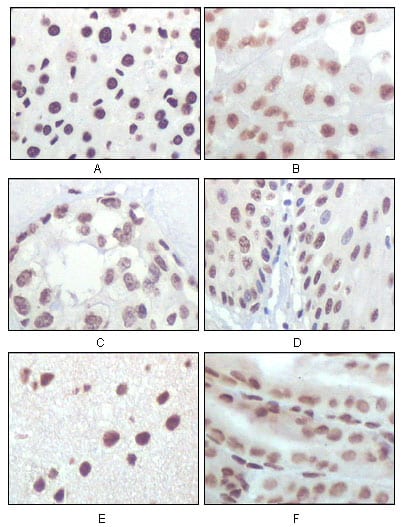

Product Image

- Immunohistochemical analysis of paraffin-embedded human prostate tissues using GSTP1 mouse mAb with DAB staining.